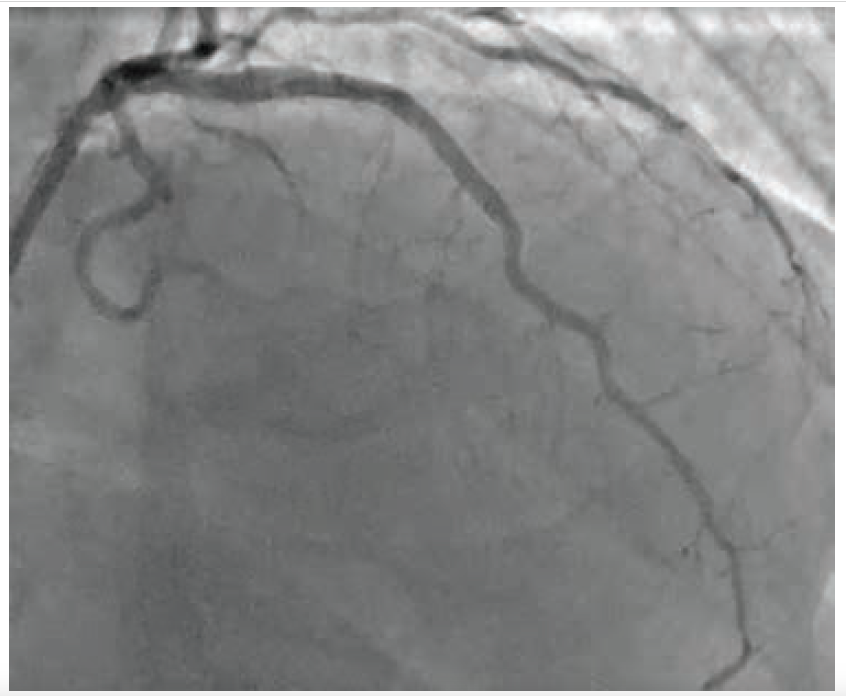

The patient is a 77-year-old male with a history of hypertension and hyperlipidemia who presented to our group at Cardiovascular Specialists of New England (CSNE) after a cardiac catheterization showed a chronic total occlusion of the proximal left anterior descending (LAD) coronary artery (Figure 1). A cardiac stress PET showed a large reversible defect in the anterior and anterolateral walls of the left ventricle. He continued to have exertional angina despite maximum medical therapy. We performed a repeat angiogram with dual injections from the right coronary artery and left main. After successful traversal of the chronic total occlusion of the LAD using a Turnpike Spiral microcatheter (Teleflex) and .014-inch Mongo wire (Asahi Intecc), 2.5 mm and 3.0 mm noncompliant balloons were unable to expand the lesion (Figure 2).